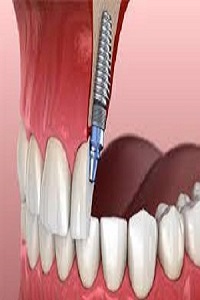

Edge Dental are a Houston city dental care clinic who are available to treat patients with any dental issues they are experiencing. Contact us today by calling (281) 940-6960 to book an appointment with our experienced dentists in Houston, TX. Justin Lai DDS, a Family and Cosmetic Dentist in Houston, is Committed to Offering comprehensive care including dental checkups, cosmetic dentistry, dental implants & orthodontics, for the Whole Family in a Relaxed Environment.